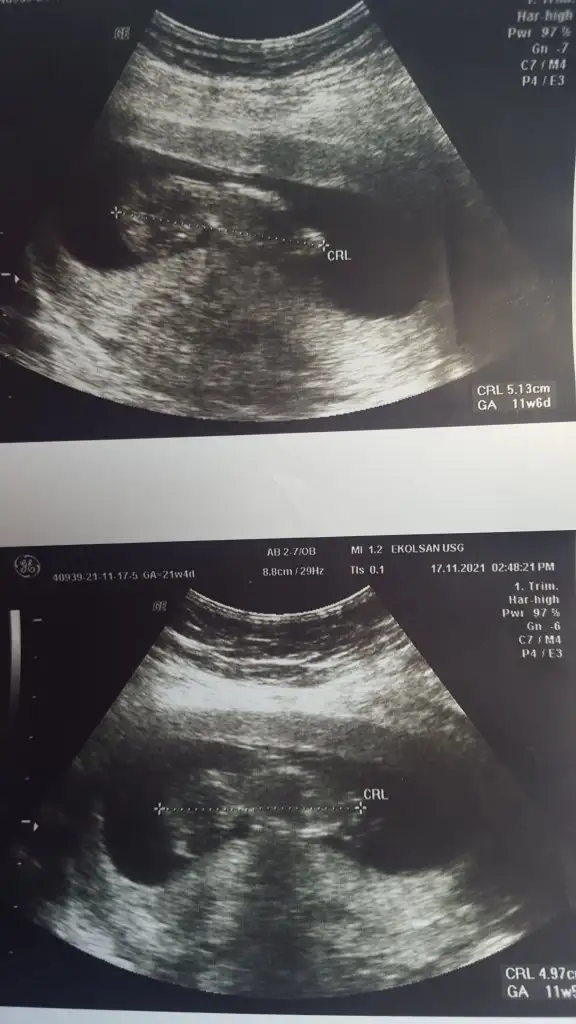

Kızlar kontrolden geldim 8+1 günlük olmuş miniğim geçen hafta 6+5 çıkmıştı. Takvimimi yakalamış 8+2 takvim. Burada korkan arkadaşlar vardı belli etmesem de ben de evhamlandım ama ilk haftalarda bunun olabileceğini çok duymuştum. Ölçümden kaynaklandığını düşünüyorum ama yine de özele de gittim devlete de başka yere de sonuç hepsi birbirinden farklı diyebilirim. Evhamlanan kızlar için yazmak istedim. İnşallah hepimizin minikleri sağlıkla büyüsün